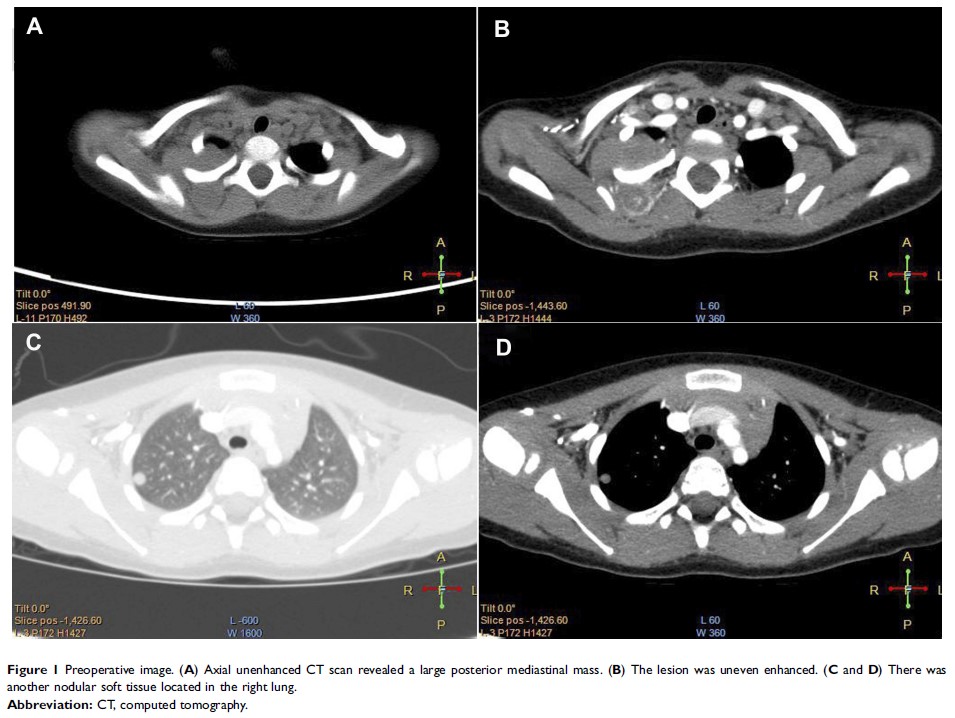

儿童恶性蝾螈瘤:病例报告和文献回顾